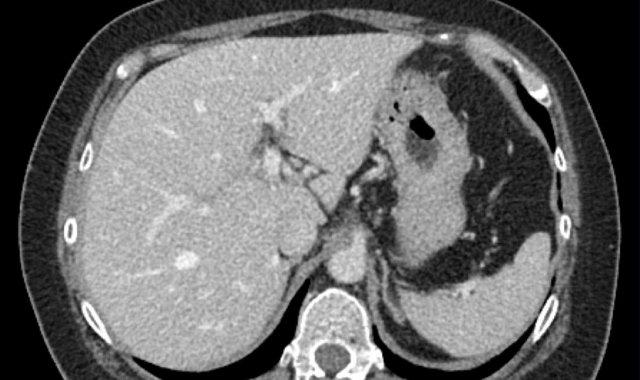

Các hình ảnh cho thấy một tổn thương ngấm thuốc động mạch có thải thuốc ở phân thùy VI, nghi ngờ HCC: LR-5.

Lưu ý rằng sự ngấm thuốc động mạch mờ nhạt do bệnh nhân được chụp ở thì động mạch sớm thay vì thì động mạch muộn – thì mà HCC đạt đỉnh ngấm thuốc.

Do đó, các tổn thương nhỏ bổ sung có thể dễ dàng bị bỏ sót.